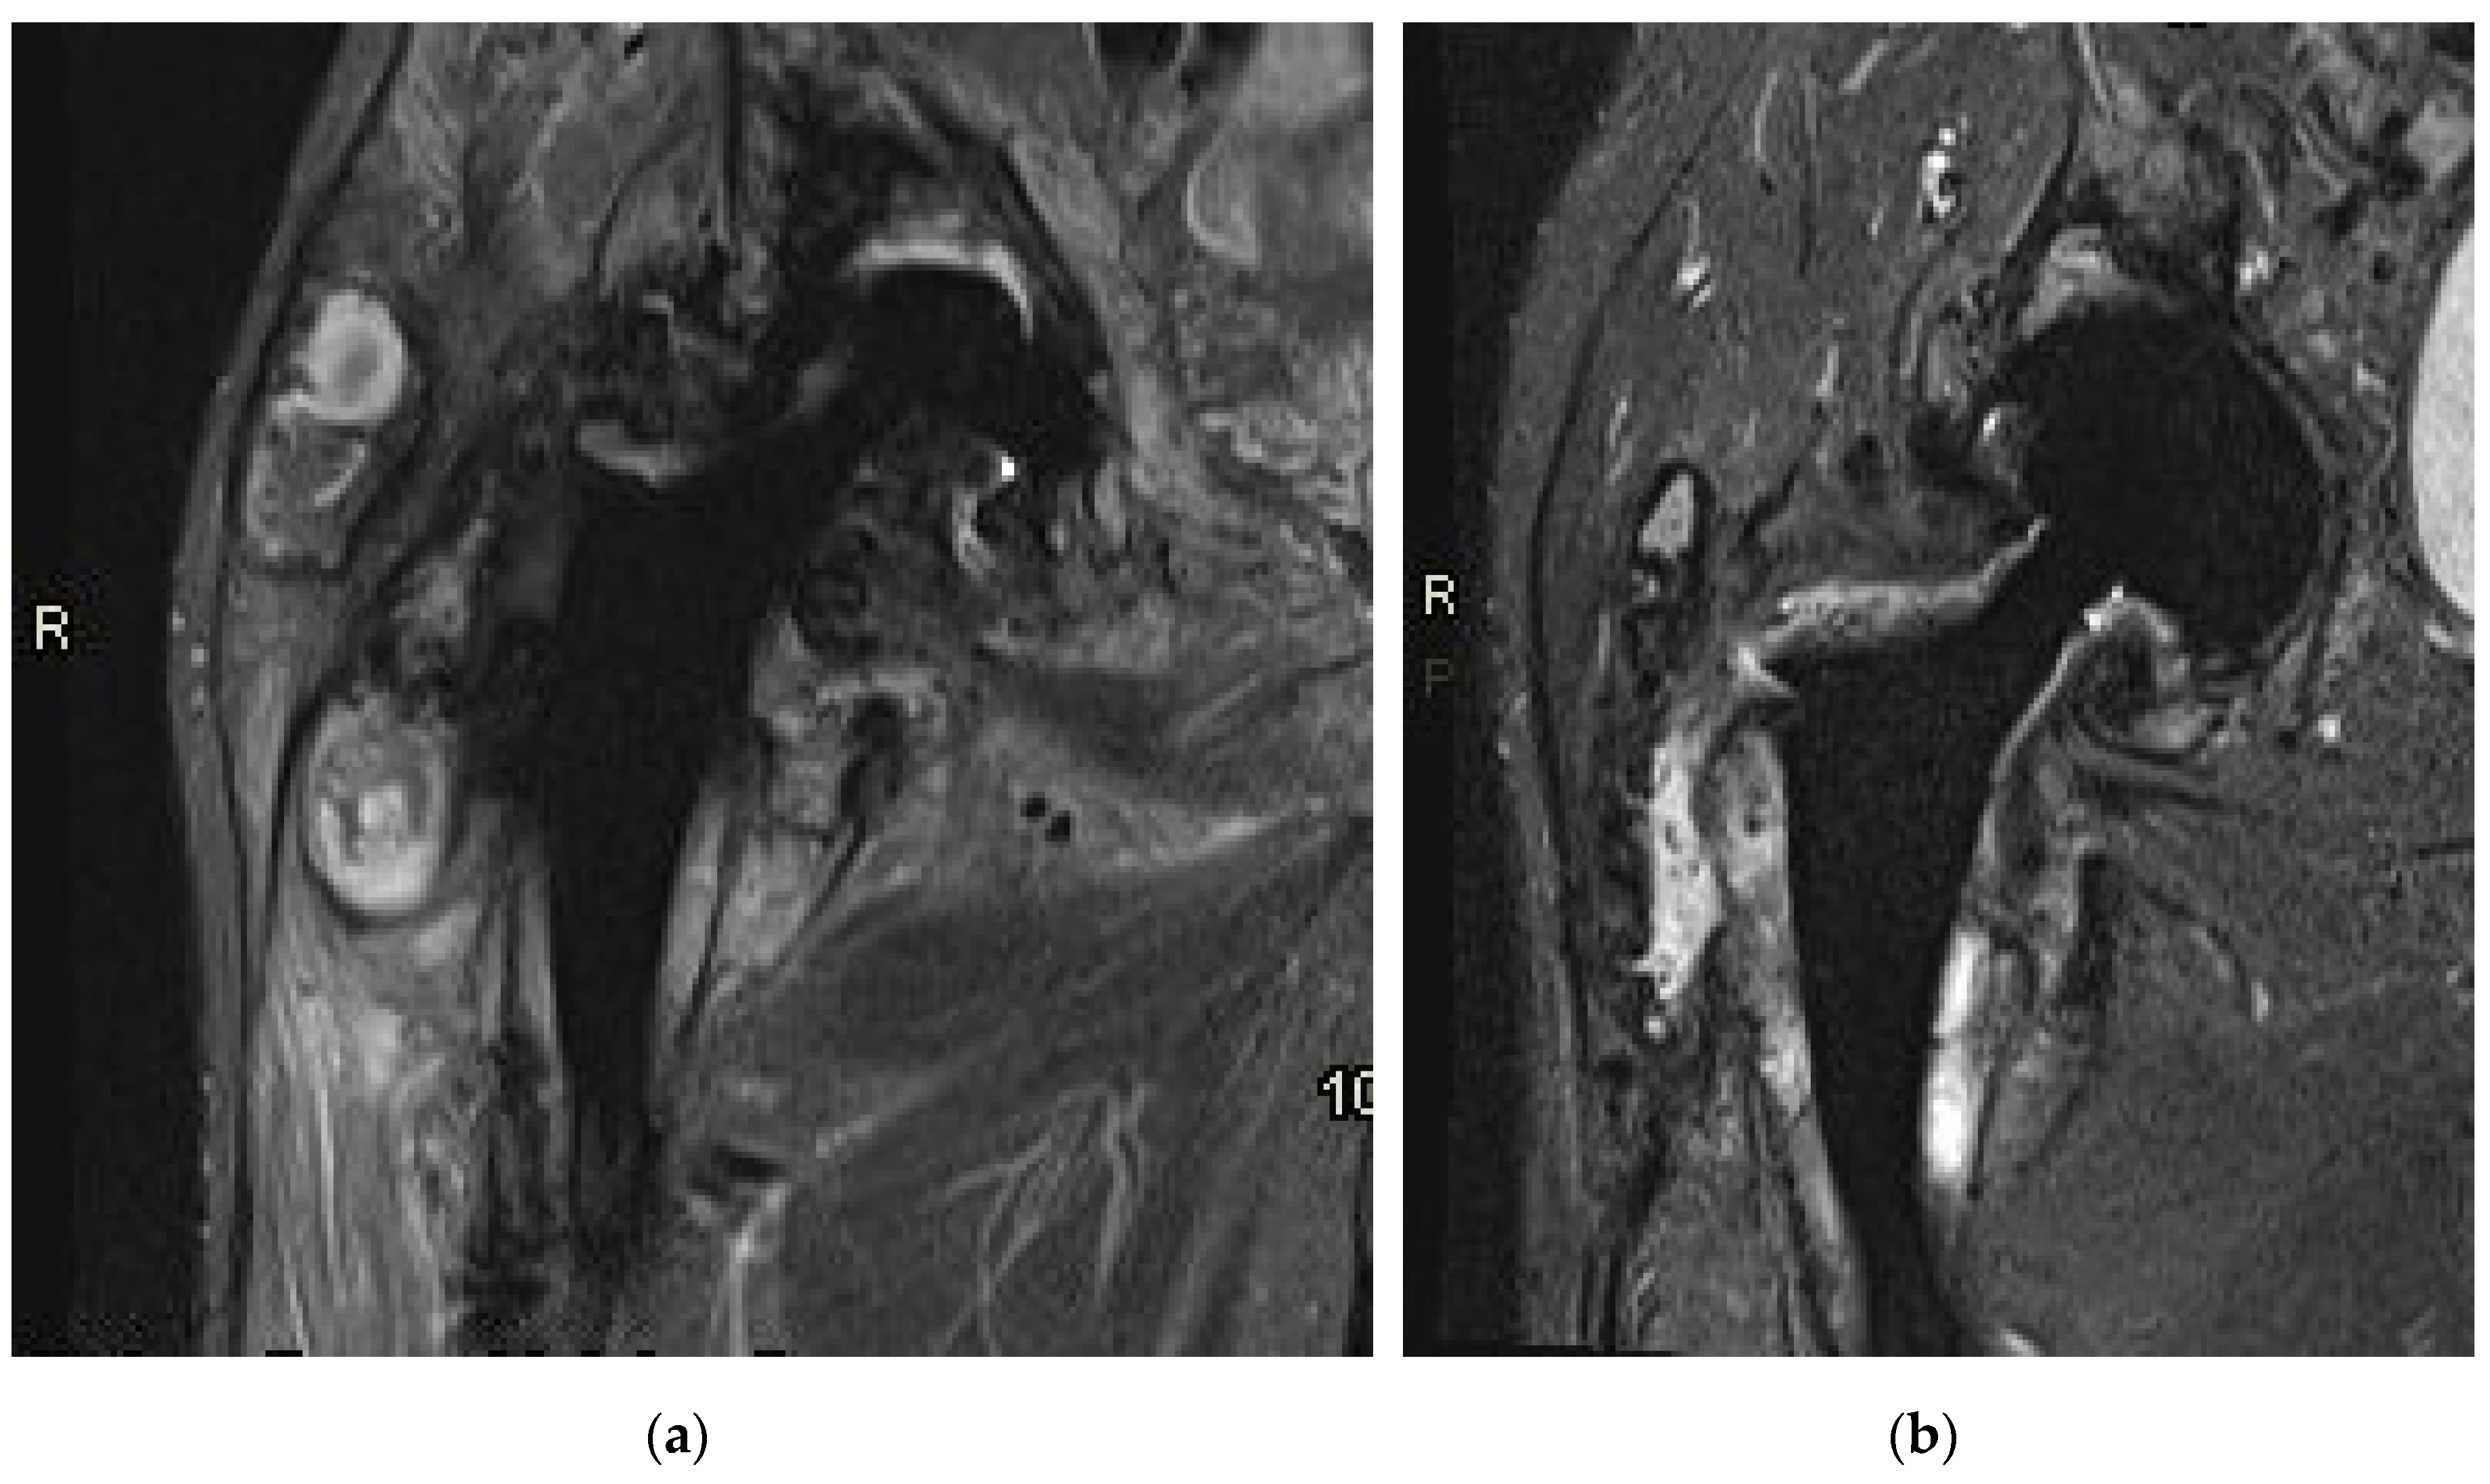

3.3. MR imaging

Prior to the revision surgery, MRI revealed substantial soft tissue alterations around the endo-prosthesis, particularly in the muscles proximal to the greater trochanter of the femur. Primarily, these changes manifested as solid chronic granulation with a smaller cystic component that was partially calcified. In both the described soft tissue changes and the periprosthetic osteolytic regions, minute hypointense inclusions of metal microparticles were observed (Figure 7a). Six months post-revision surgery, the previously extensive granulation changes in the surrounding soft tissues were diminished. There was reduced soft tissue edema, and indications of local irritation had also decreased. The presence of slightly increased fluid around the endoprosthesis indicated residual seroma following the surgery (Figure 7b).

Figure 7. Magnetic resonance imaging (MRI) of the right hip in coronal plane. (a) Before revision; (b) Six months after revision surgery.